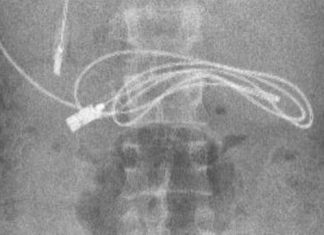

Turqi: 15-vjeçarit mjekët ia heqin nga barku adapterin e telefonit (VIDEO)

Mjekët mbetën të shokuar. Ajo se çka panë në skaner ishte jo e zakonshme. Brenda stomakut të një 15-vjeçari u gjet një kabllo të adapterit të telefonit.

Rasti i çuditshëm ndodhi në Turqi. Adoleshenti ishte...